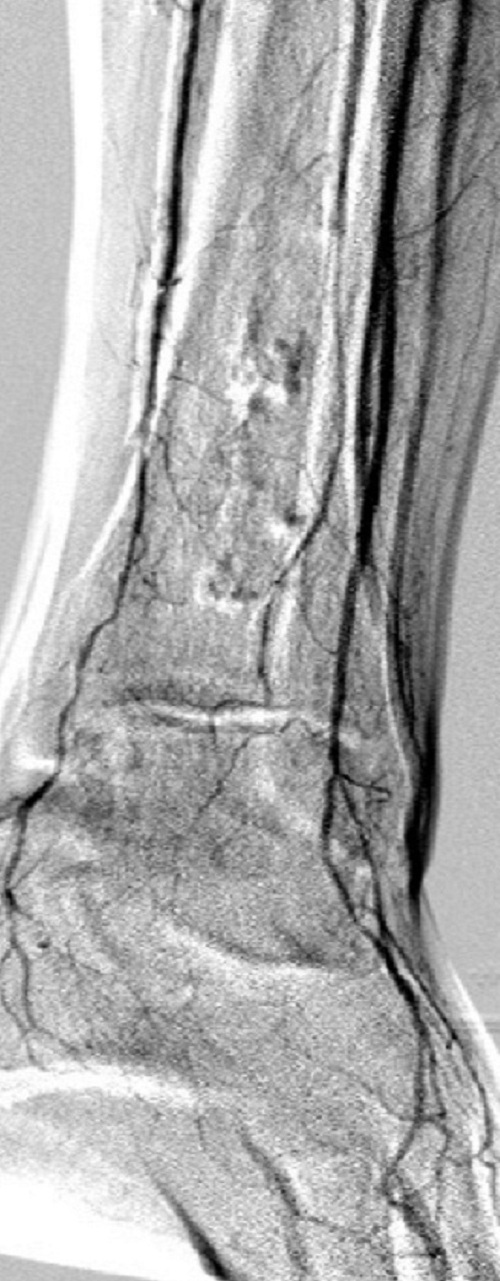

Bottom panel: Post intervention run-off arteriogram of the left lower extremity showing, from left to right, the proximal and distal segments of the re-opened left femoro-popliteal bypass (red arrows on images 1, 2, and 3). Contrast the full-column opacification of the below-knee left popliteal artery, arrowed blue on the 3rd image, and the enhanced visibility of the three-vessel subpopliteal domain to their vestigial appearances on the pre-intervention images, when they were poorly fed through collaterals.

When blood flow into or out of a bypass fails, it thromboses and its salvage includes gaining access into it and removing the clot in addition to determining the reason for its failure. Such clot removal may be mechanical, as is frequently the case in acute graft failure, or through thrombolysis, as is the case in later failures. The above images illustrate the later scenario in which the patient presented about 1 year after a left femoropopliteal bypass was fashioned for them. I crossed into the lumen of the bypass conduit from a right common femoral arterial puncture and advanced an infusion cather into it for overnight continuous alteplace infusion following a bolus dose. (I favor 5 to 10 mg of alteplace bolus, followed by continuos infusion at 0.5 mg per hour, in company with fixed unfractionated heparin infusion at 500 units to 600 units per hour after a bolus dose of 3000 units to 5000 units). In this case the bypass proved to be a vein conduit connecting the left common femoral artery, proximally, to the mid popliteal artery, distally, without intimal hyperplasia. The cause of the failure was diminished inflow due to left iliac disease.The final runoff images reveal a three-vessel tibial domain continuous with a near-normal plantar arch.